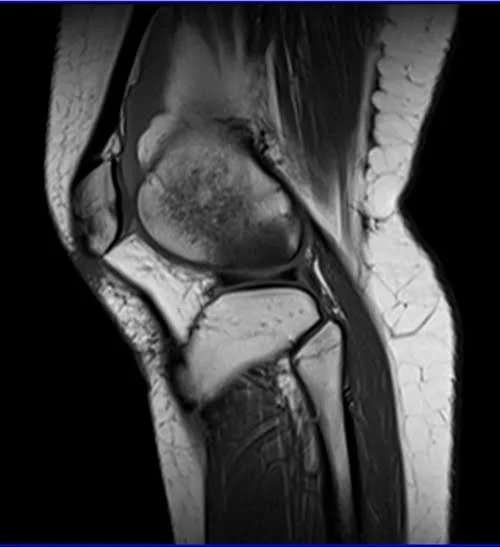

MRI knee sagittal t1 3 - MRI